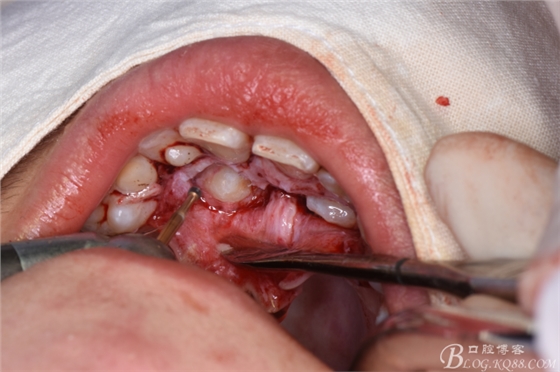

圖9.初步顯露13牙冠

圖10.球鉆修整23牙冠周圍骨質(zhì)

圖11.球鉆修整13周圍骨質(zhì)

圖12.修整完成后的13、23牙冠暴露情況

圖13.光固化粘接23托槽

圖14.分別在13、23牙冠上粘接帶有橡皮鏈的托槽

圖15.拔除63乳牙

圖16.分別拔除53、63后,縫合腭側(cè)黏膜瓣,橡皮鏈從牙槽嵴頂穿出。

圖17.縫合完成的唇面觀,橡皮鏈從牙槽嵴頂穿出。